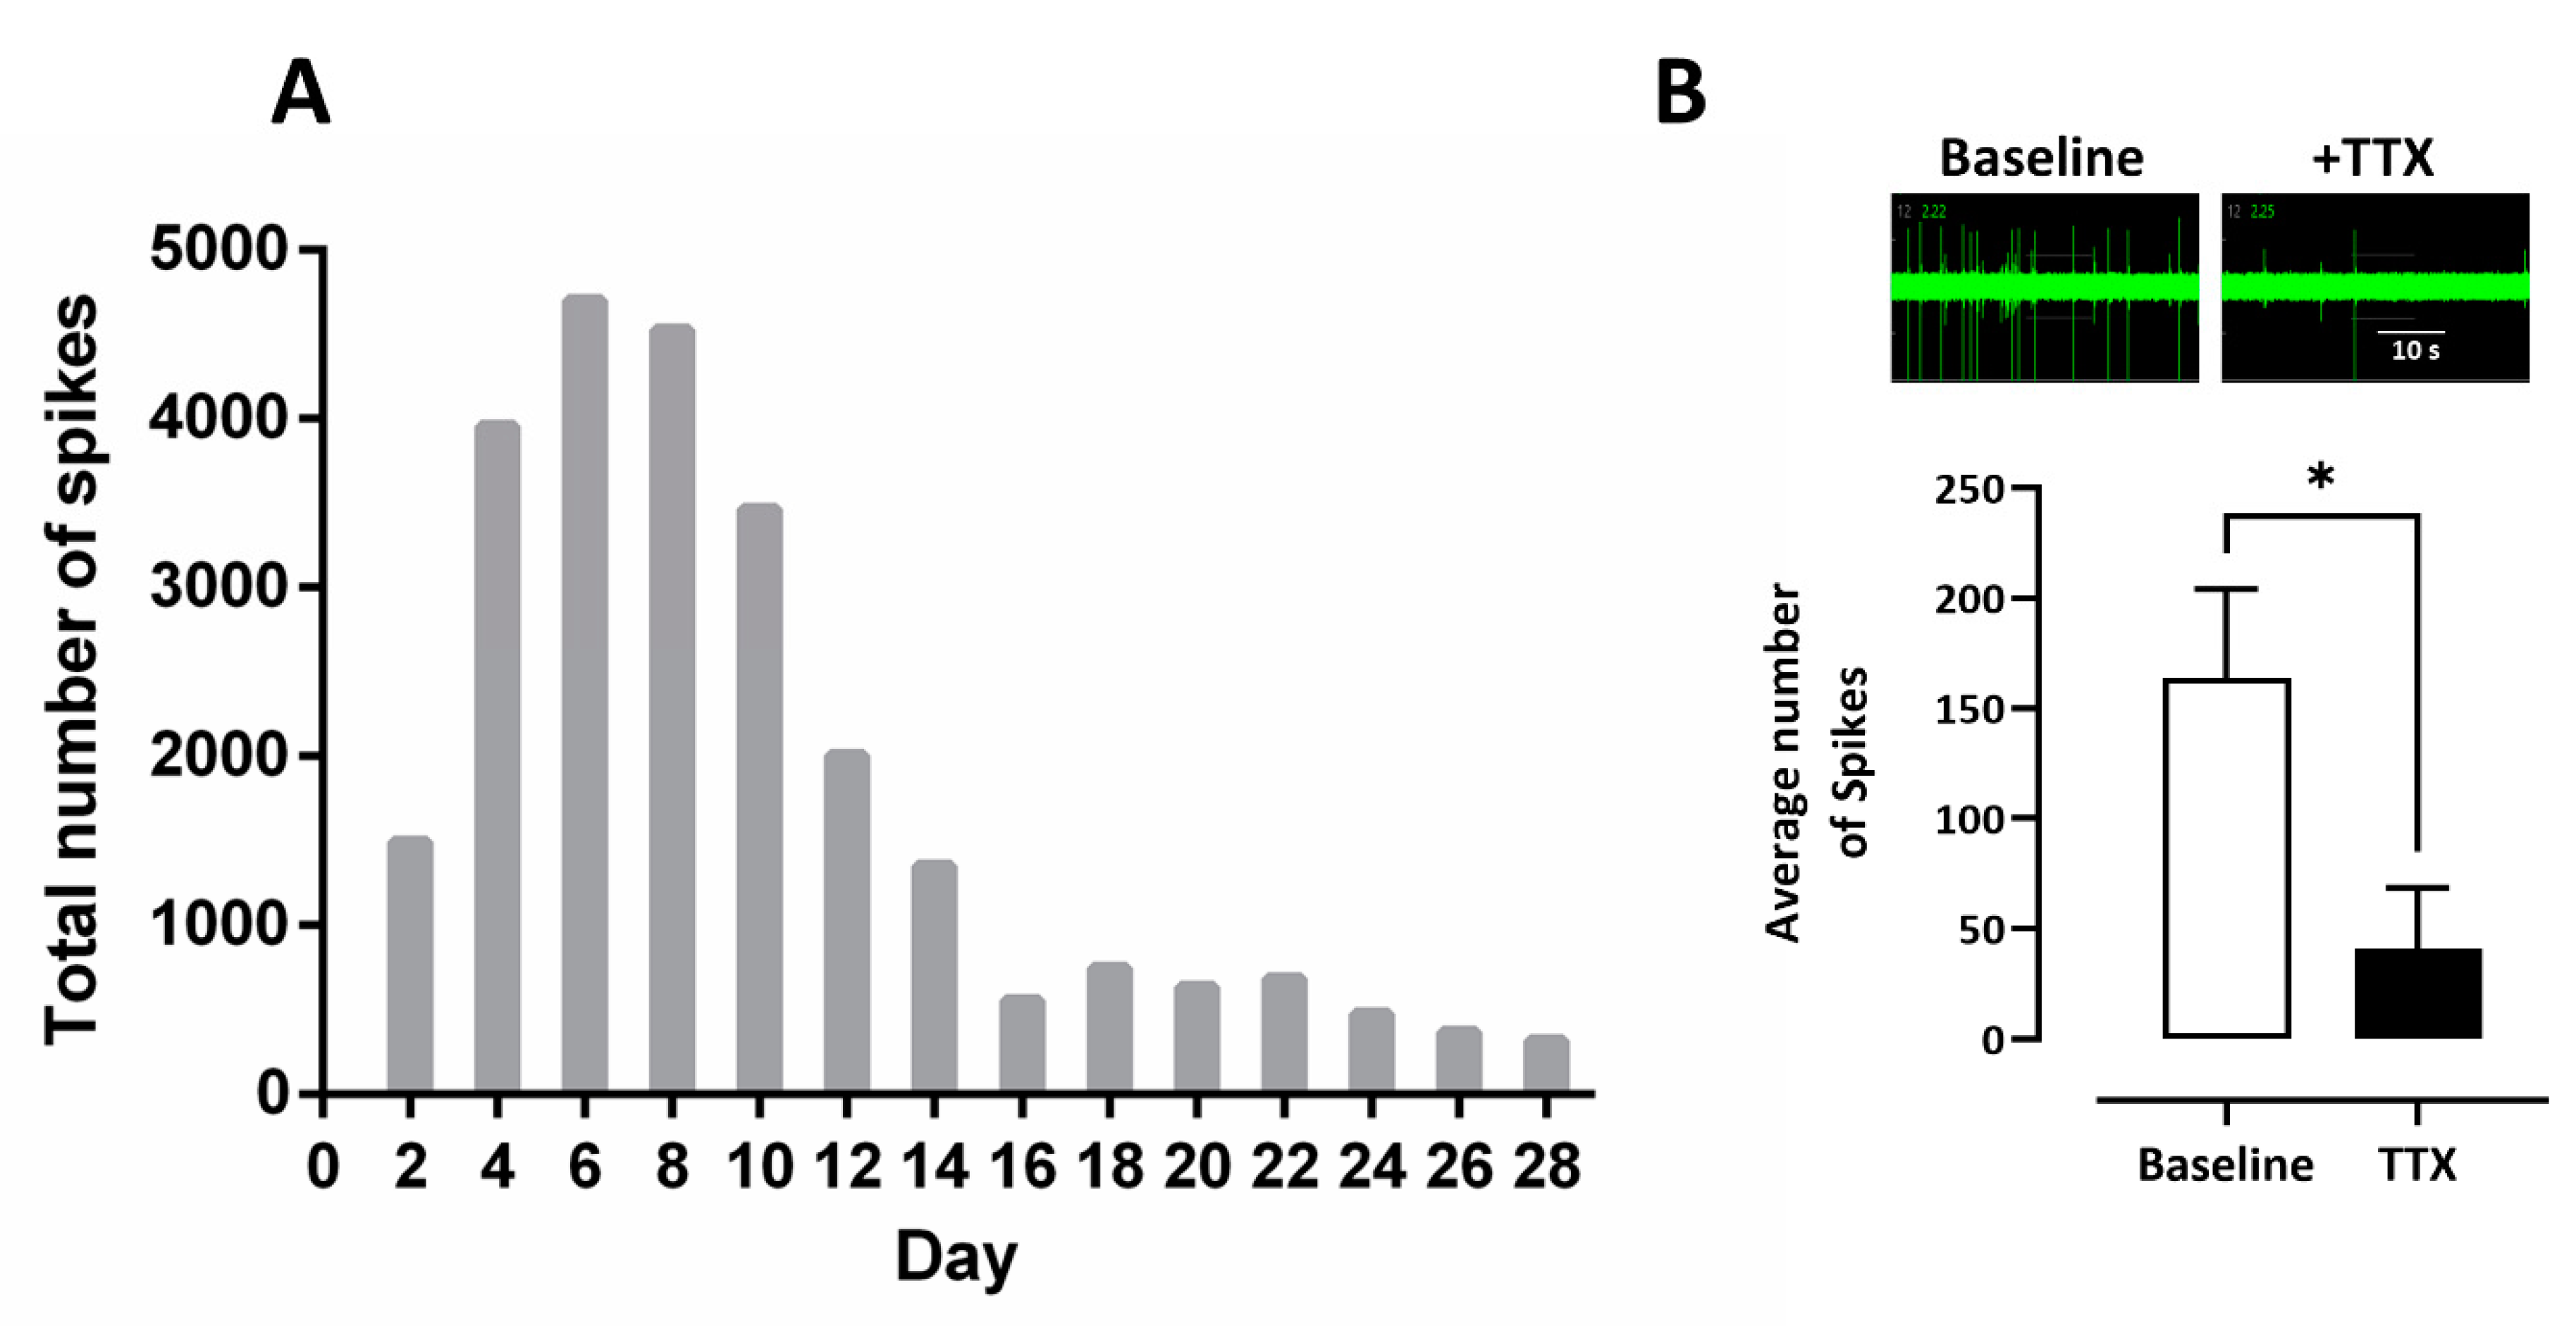

2.3. Multi-Electrode Array Electrophysiology

3.1. Multi Electrode Array